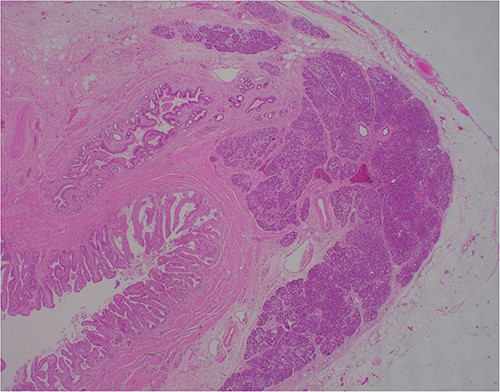

At outpatient phone clinic review 2 months post-surgery, the patient had recovered well, and his pre-operative symptoms of nausea, vomiting and pain had completely resolved. The histopathology of the gallbladder found chronic cholecystitis with cholelithiasis, in addition to a 6 mm focus of pancreatic heterotopia in the gallbladder wall. This heterotopic tissue contained acini, ducts and islet cells, classifying it as Type I pancreatic heterotopia (Figs 1–3).

×20 objective lens; normal duct towards left hand side; acini (with dense pink cytoplasmic granules) and islets (clusters of pale cells).